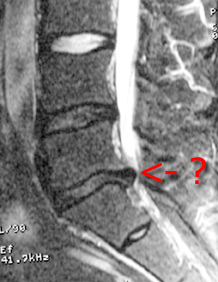

It seems I have a herniated disk in my lower back. That would explain why I have taken to laying on my side on the floor and praying for death.

In fact, in spite of the banging noises of the machine, I even fell asleep briefly. The doctor hasn’t seen the film yet, so I have been trying to interpret it by myself. So far I have been able to confirm that I do, in fact, have a spine, and some areas of it look, to my untrained eye, ouchy.

Update: The doctor still hasn’t seen the films, but the imaging office sent a preliminary diagnosis. It was not a nice one.